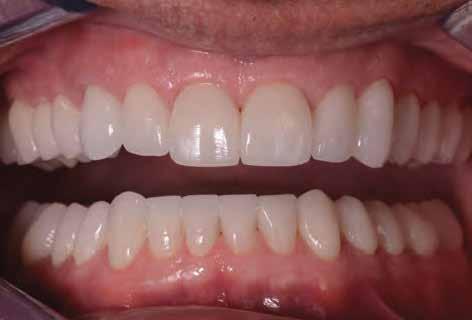

ÚJ PARADIGMA AZ ESZTÉTIKAI HELYREÁLLÍTÁSBAN

Fontfogak esztétikai helyreállítása KATANA™ UTML teljesen anatómikus koronákkal, vesztibuláris leplezéssel és Biológiailag

Dr. Marco Nicastro (Olaszország) A kiindulási állapot és a végeredmény. A KATANA™ UTML kiváló esztétikai tulajdonságokkal rendelkezik, és tökéletesen, harmonikusan illeszkedik a rózsaszín szövetekkel.

16. ábra: Klinikai fotó egy évvel a PANAVIA V5-tel történő beragasztás után. A marginális szövetek jó klinikai állapotát látjuk, semmi jele gyulladásnak vagy vérzésnek. A BOPT lehetővé teszi számunkra, hogy optimalizáljuk a gingiva szintjét anélkül, hogy parodontológiai sebészeti beavatkozáshoz folyamodnánk, miközben az új koronák alakja lehetővé tette az interproximális terek zárását az optimális esztétikai eredmény érdekében.

17. ábra: A fogpótlás világossága (főleg a transzlucentes cirkónium használatának köszönhetően), a metszők alakjával kombinálva nagymértékben javította a pótlás esztétikáját, még akkor is, ha a kiindulási helyzet különösen kedvezőtlennek tűnt.

18. ábra: Az előző fogpótlással összehasonlítva a metszők redukálása nem csak azt tette számunkra lehetővé, hogy optimalizáljuk a funkcionális fázist az overjet csökkentésével, hanem lehetővé tette a még esztétikusabb eredmény elérését azzal, hogy a metszők élének kontúrjával követni tudtuk az alsó ajkat.